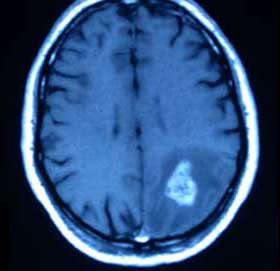

Ese fue el primer episodio en el que Emma se desconcertó profundamente. Después vivió 3 momentos parecidos. Justin visitó a varios especialistas y se realizó varios estudios. El diagnóstico no fue alentador. Justin tenía un tumor cerebral.

Justin se sometió a diferentes tratamientos y los médicos le daban máximo 2 años de vida. Emma sufrió mucho estrés por lo que su parto se adelantó y su bebé nació 5 semanas antes de la fecha prevista.

Su pequeñita nació en perfectas condiciones, pero desafortunadamente la salud de Justin no mejoró, el tumor hizo metástasis. La pareja estaba devastada, entonces, Emma decidió hacer todo lo que estaba en sus manos para que Justin fuera muy feliz los últimos días que le quedaban.

Desde que a Justin le diagnosticaron el tumor, vivió 7 meses más. Logró celebrar la Navidad y festejar su cumpleaños número 30.

Emma ha decidido compartir su historia para crear conciencia sobre los síntomas de este tipo de tumores. Después que Justin falleció, encontró una fotografía donde su rostro estaba notablemente caído de un lado, era un signo de su enfermedad.